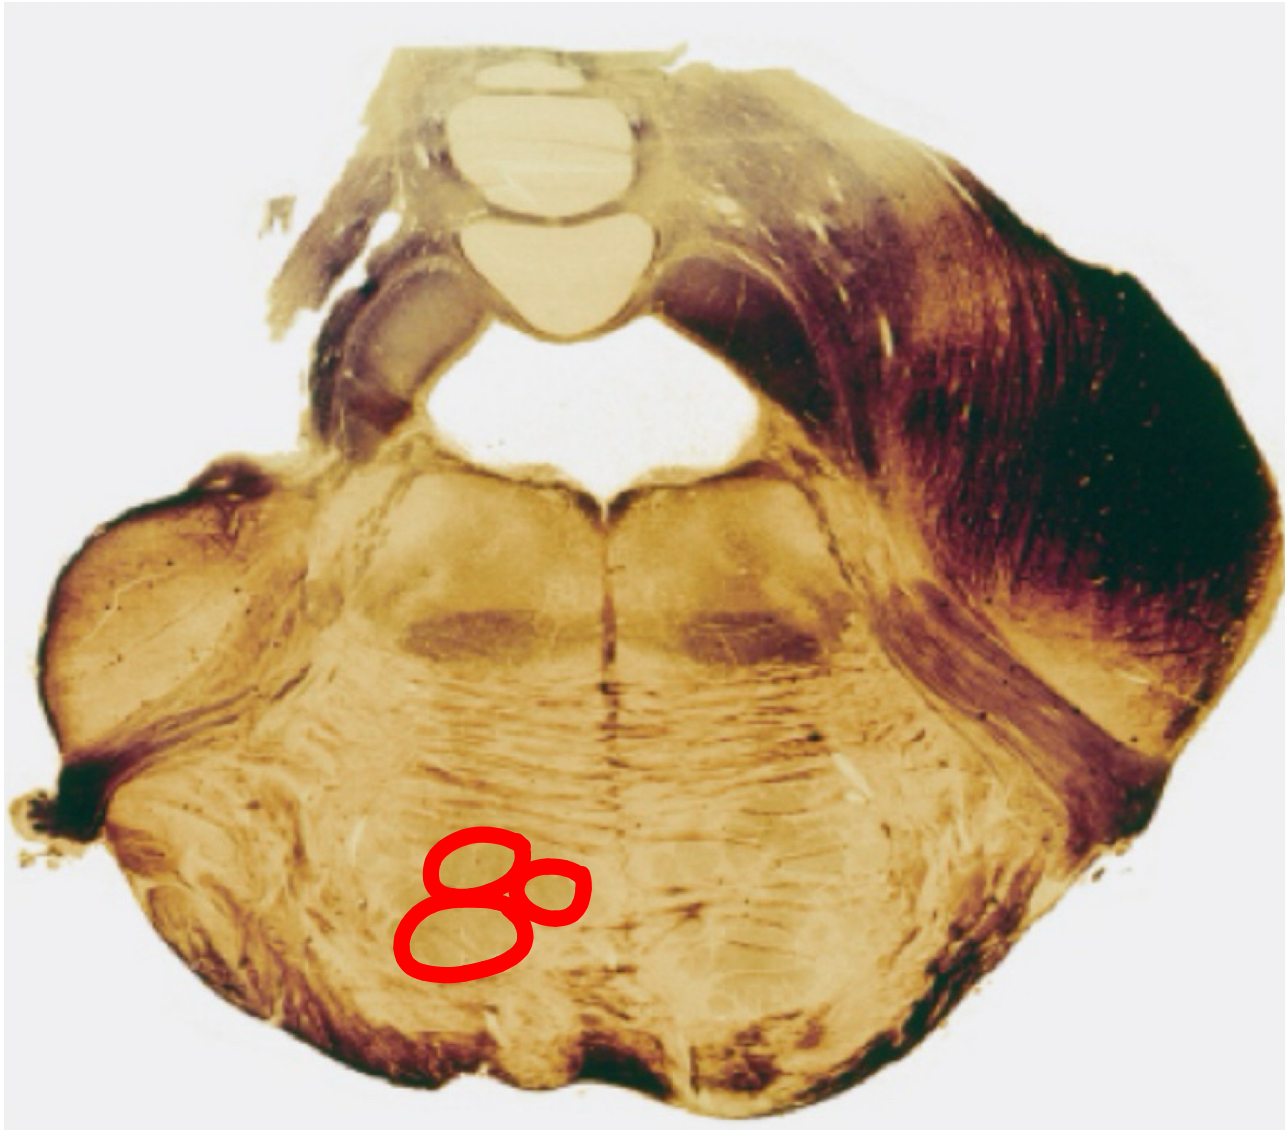

decussation of the pyramids caudal medulla I

pyramids caudal medulla I

gracile tract caudal medulla II

gracile nucleus caudal medulla II

cuneate tract caudal medulla II

cuneate nucleus caudal medulla II

spinal tract of trigeminal caudal medulla II

trigeminal sensory nucleus

pyramids caudal medulla II